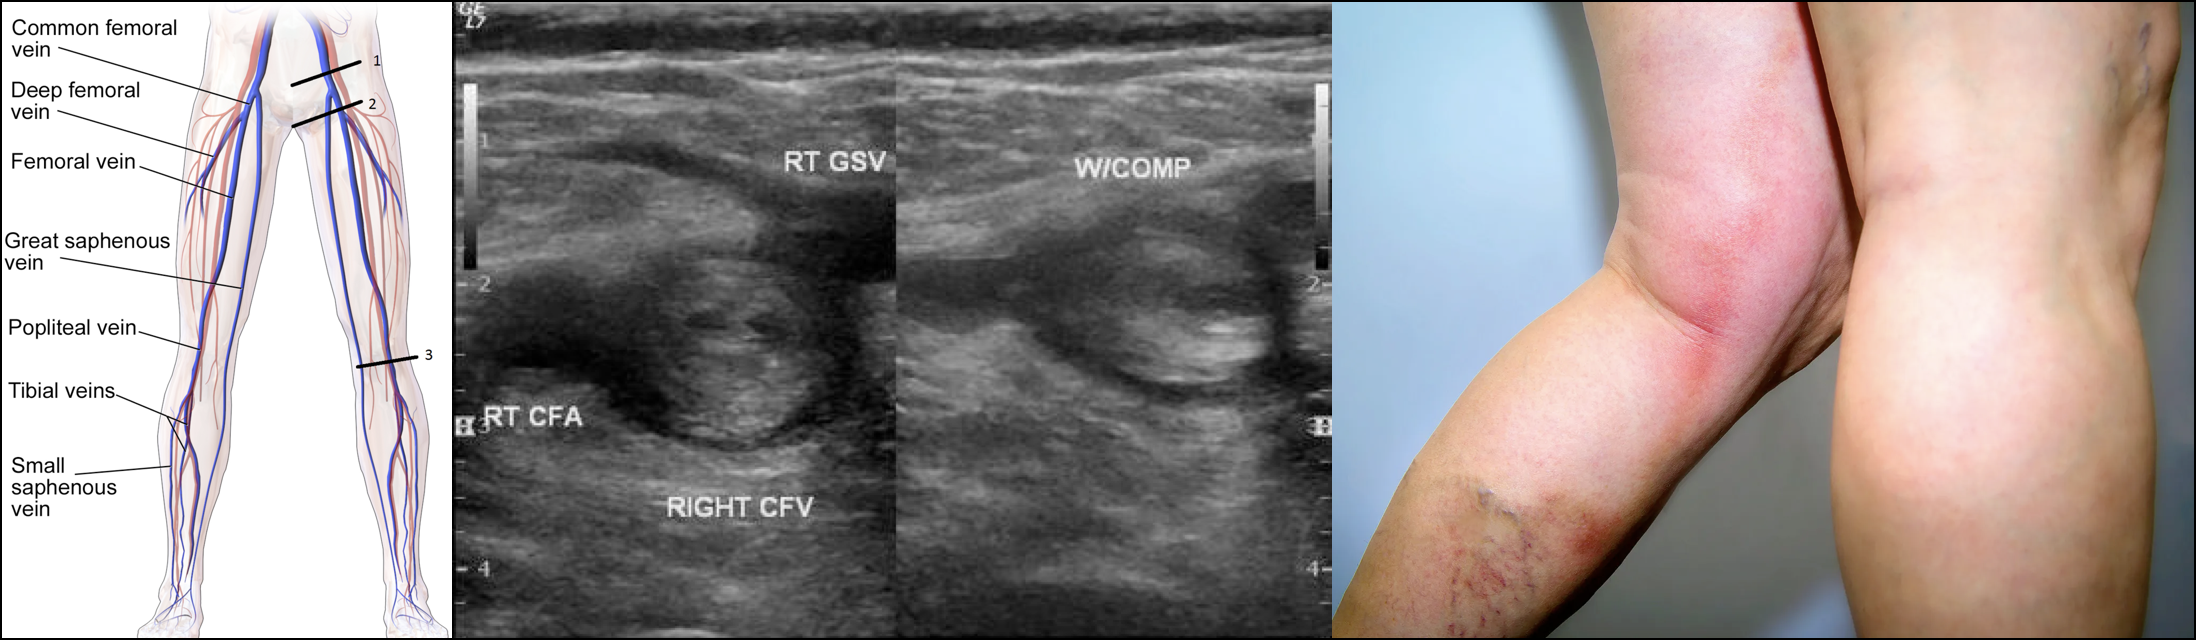

Venous Anatomy

◾️Knowledge of the venous anatomy is crucial for the following reasons:

- For the performance and interpretation of the ultrasound of the leg veins

- The anatomic location of a DVT also influences prognosis because proximal DVTs are less likely to lyse spontaneously, more likely to embolize, and are associated with a greater risk of long-term complications such as post-thrombotic syndrome.

- The probability that a DVT will cause a PE depends significantly on the location of the thrombus.

◾️The anatomy of the extremities’ veins is shown in the figures below.

- Deep veins of the lower extremity

- The deep venous system includes the anterior tibial, posterior tibial, and peroneal veins, collectively called the calf veins *.

- Venous thrombi isolated to the calf veins are referred to as distal DVT.

- The calf veins join together at the knee to form the popliteal vein, which extends proximally and becomes the femoral vein at the adductor canal *.

- Venous thrombi in the popliteal or more proximal veins are referred to as proximal DVT.

- The femoral vein (previously known as the superficial femoral vein) is joined by the deep femoral vein and then the greater saphenous vein to form the common femoral vein, which subsequently becomes the external iliac vein at the inguinal ligament *.

- Venous thrombi in the proximal femoral and iliac veins are known as iliofemoral DVT.

- Superficial veins of the lower extremity

- In the lower extremity, the superficial venous system consists primarily of the greater and short saphenous veins and perforating veins *.

- Distal greater saphenous vein thrombi are often referred to as superficial thrombosis, but greater saphenous clots near the connection with the femoral vein should be referred to as DVT.

Venous Ultrasound

◾️DVT is characterized on US by the presence of heterogeneous echogenic materials filling the deep veins, indicative of thrombus formation *. On Doppler US, a decrease or absence of venous flow in the Doppler waveform patterns may further support a DVT diagnosis. One of the US findings indicative of DVT is decreased compressibility of the affected vessel. Normally, vessels should flatten when compressed under a US probe. However, in veins affected by DVT, the thrombus may prevent compression. While some cases of DVT involve the entire lumen and maintain a round shape under compression, partial DVT may cause the veins to deform but still include non-compressible areas where the thrombus is present.

- This is the criterion standard and combines compression US of the proximal veins with ultrasound of the calf and saphenous veins *.

- Three-point US, also called compression US (SN 95% and SP 95% for DVT).

- Scans the common femoral, femoral, and popliteal veins *.

- Compression ultrasound, including the femoral vein 1 to 2 cm above and below the saphenofemoral junction and the popliteal vein up to the calf veins confluences *.